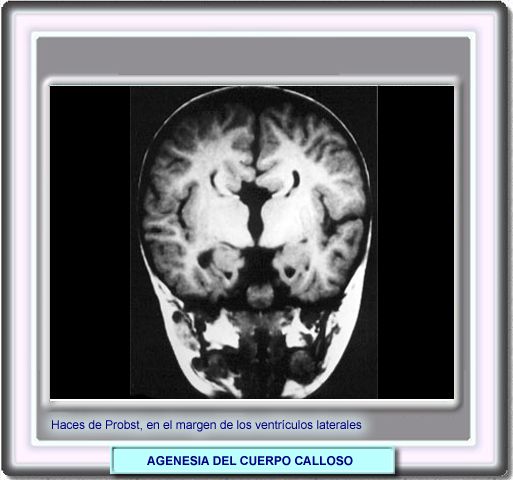

AGENESIA DEL CUERPO CALLOSO

Los haces de Probst son fascículos de fibras nerviosas que bordean los ventrículos laterales y que proceden de las fibras callosas que normalmente interconectan ambos hemosferios.